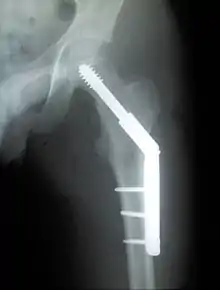

Trochanteric fracture

Fracture supported by dynamic hip screw

A trochanteric fracture, below the neck of the femur, has a good chance of healing.

Closed reduction may not be satisfactory and open reduction then becomes necessary.[32] The use of open reduction has been reported as 8-13% among pertrochanteric fractures, and 52% among intertrochanteric fractures.[33] Both intertrochanteric and pertrochanteric fractures may be treated by a dynamic hip screw and plate, or an intramedullary rod.[32]

The fracture typically takes 3–6 months to heal. As it is only common in elderly, removal of the dynamic hip screw is usually not recommended to avoid unnecessary risk of second operation and the increased risk of re-fracture after implant removal. The most common cause for hip fractures in the elderly is osteoporosis; if this is the case, treatment of the osteoporosis can well reduce the risk of further fracture. Only young patients tend to consider having it removed; the implant may function as a stress riser, increasing the risk of a break if another accident occurs.